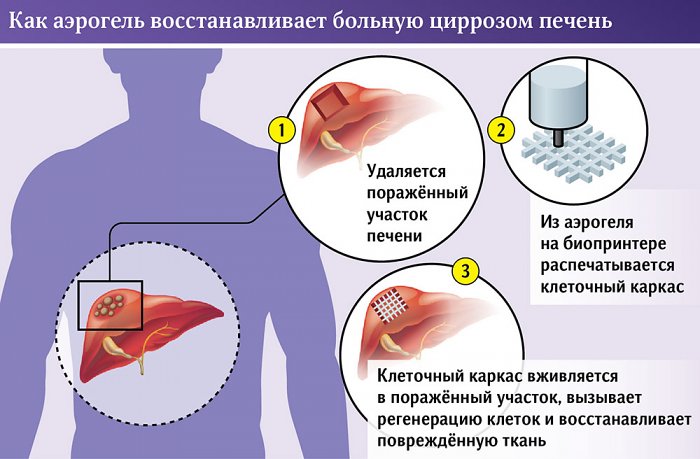

В РХТУ предложили лечить цирроз печени с помощью аэрогеля

Российскими учеными из РХТУ им.Менделеева ведется разработка перспективной методики лечения цирроза печени, в основе которой лежит особый пористый материал, названный аэрогелем и создающийся из биополимера хитозан. Из него будет изготавливаться клеточный каркас, который заменит поврежденную часть органа.

Каркас из аэрогеля будет печататься индивидуально для каждого конкретного человека, напитываться антибиотиками для подавления воспалительных процессов и стволовыми клетками пациента, а после имплантации он начнет стимулировать восстановление собственной ткани человеческого организма.

Для создания данных каркасов в РХТУ уже создан специализированный биопринтер, сам аэрогель успешно испытан на крысах, но до полноценного внедрения данной методики в медицинскую практику еще далеко — разработку ждут длительные исследования доклинического и клинического характера, да и тесты на людях могут выявить какие-нибудь «подводные камни».